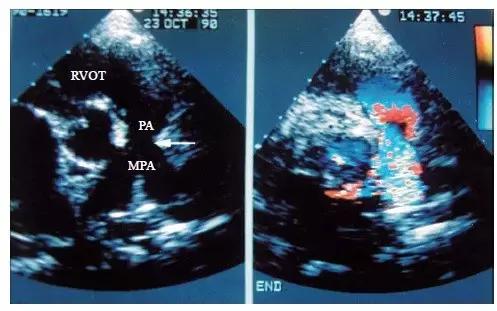

3.由于法洛四联症患者的漏斗隔前移,因此还可见右心室流出道明显缩小,右心室壁和右心室流出道壁明显增厚。在肺动脉长轴切面上,可显示大多数患者肺动脉瓣瓣环和肺动脉主干较细,其程度是决定是否进行跨肺动脉瓣瓣环补片手术的重要因素。合并肺动脉瓣狭窄的患者还可见肺动脉瓣增厚,开放受限,收缩期呈圆隆状。

4.彩色多普勒血流显像显示肺动脉内有五彩镶嵌的细窄射流束,提示肺动脉瓣口狭窄。射流束近端的直径取决于肺动脉瓣狭窄的程度,狭窄越严重,射流束就越细。然而必须明确的是,在肺动脉口重度狭窄的患者,肺动脉内有时可无明显血流信号存在。肺动脉瓣上狭窄的患者肺动脉主干内可见有嵴状凸起。